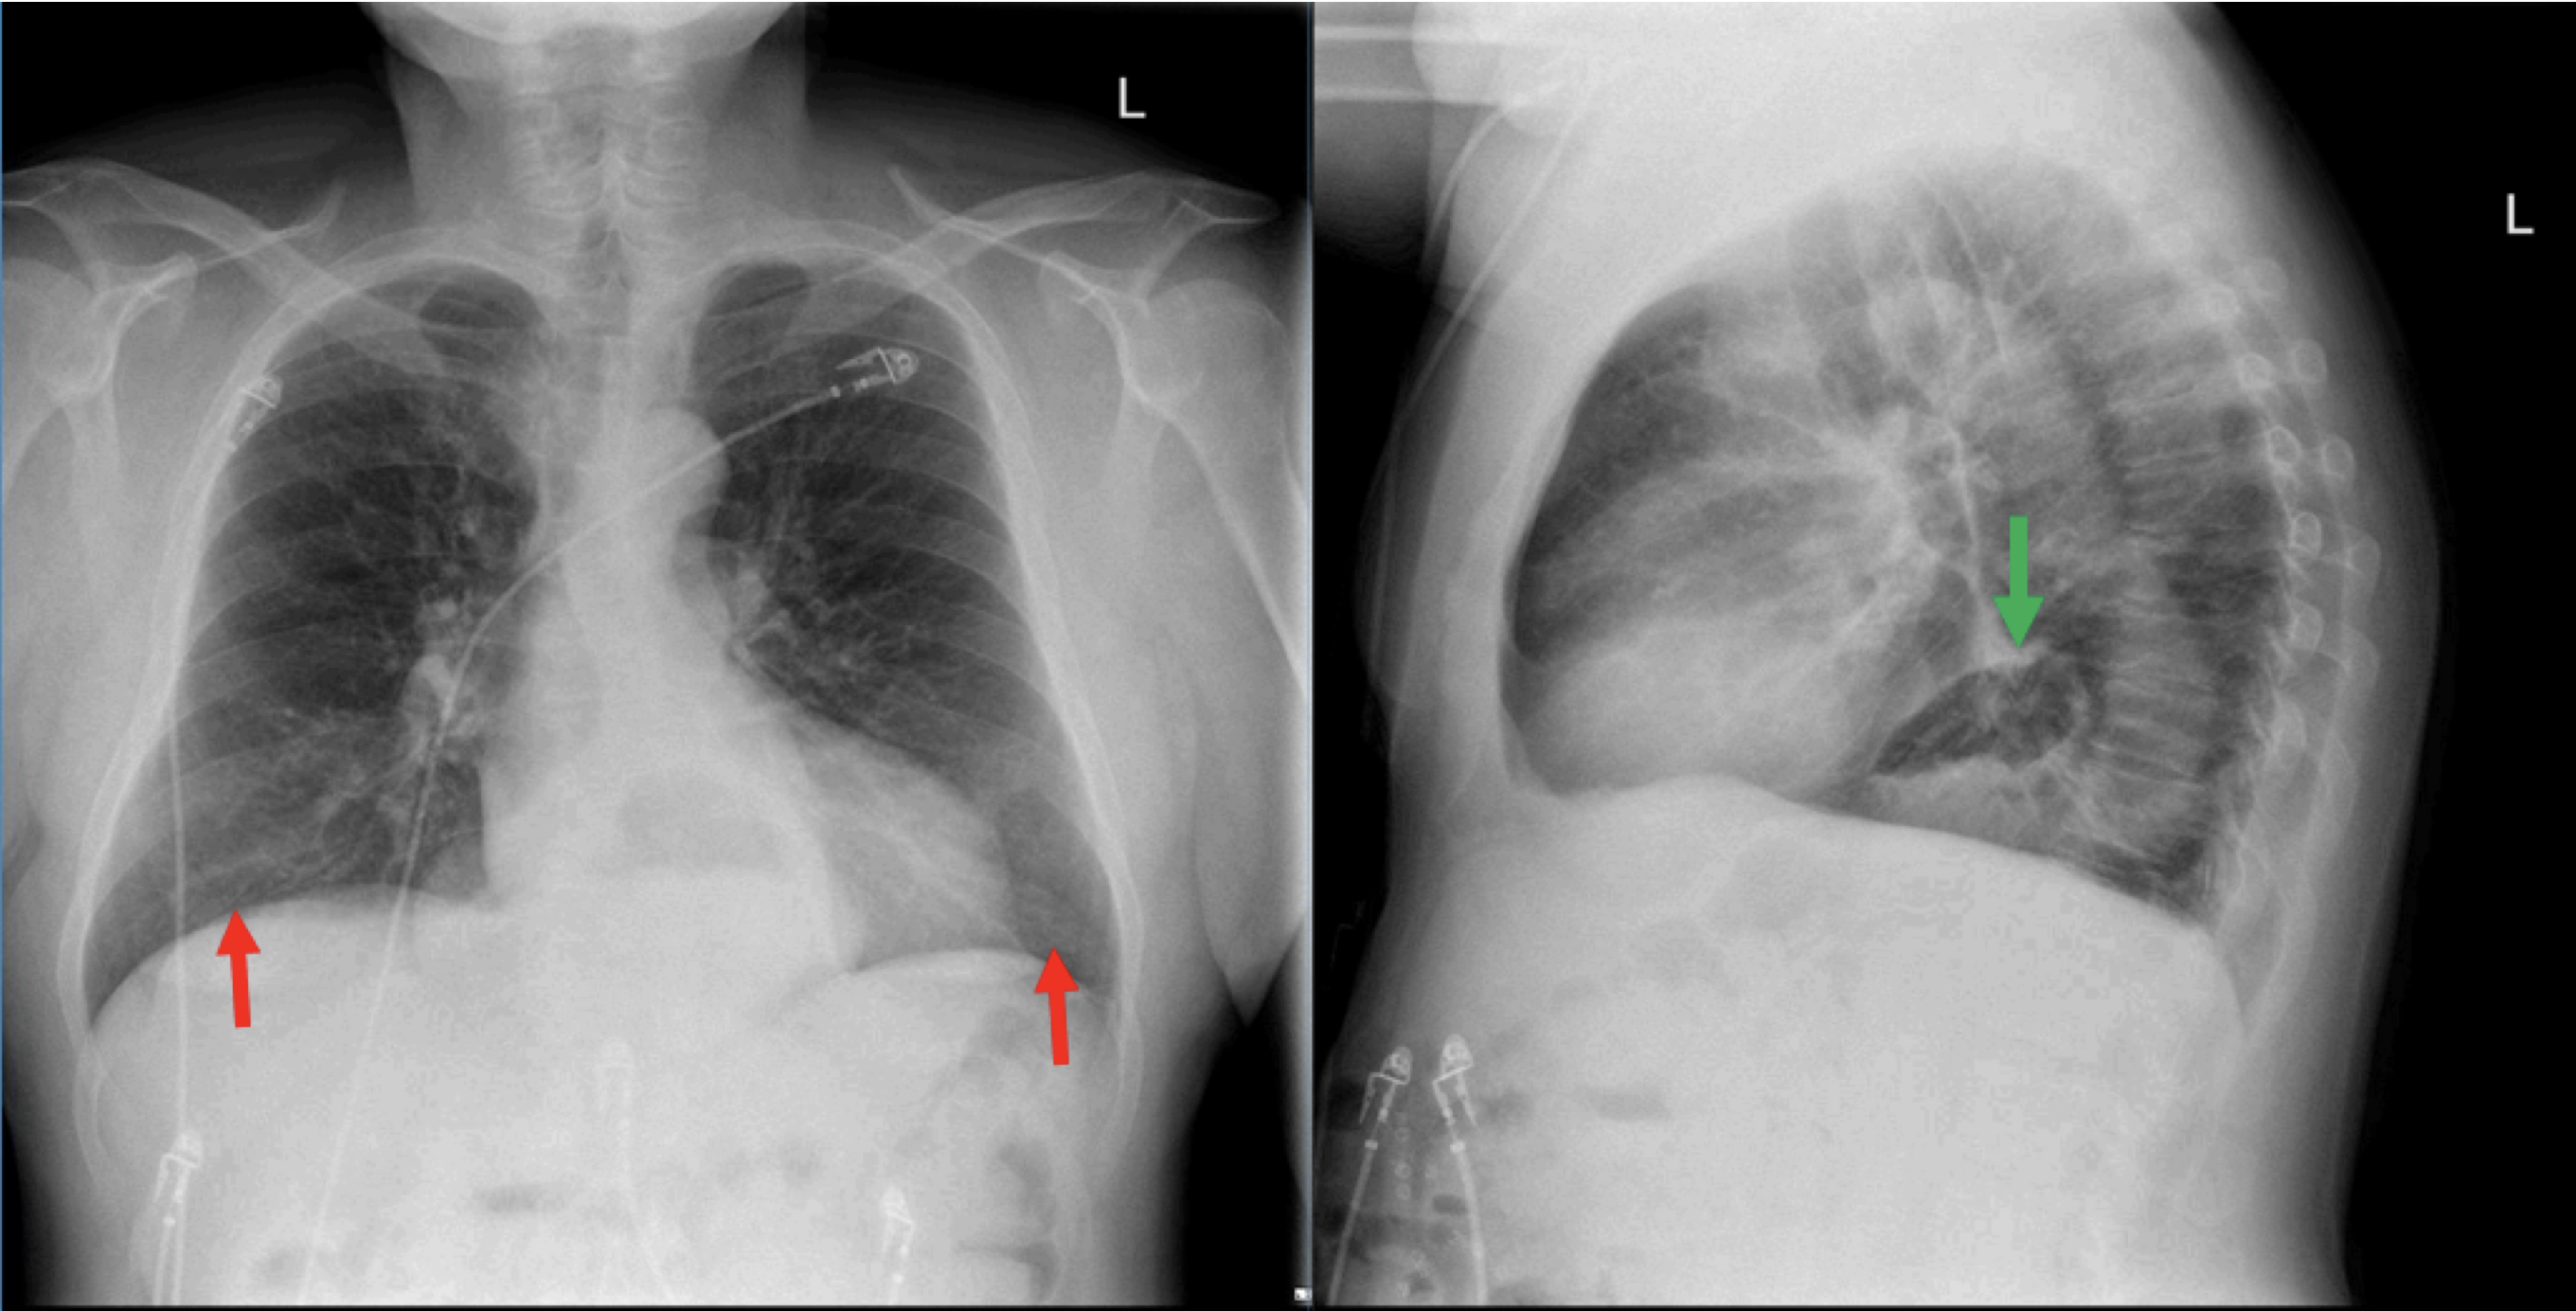

Epidemiology gastric diverticula are rare and c. Weight loss surgery is about reducing your weight and gaining good health. Gastric diverticula are sac like projections that usually originate from the gastric fundus most commonly on the posterior surface. They are the least common of the gastrointestinal diverticula.

Cain jc jordan gl jr comfort mw gray hk. J am med assoc. The gas tric fundus is dened as the portion of the stomach craniad to the gastric car dia. Commonly accompanying this are abnormally dilated short gastric veins which pass from the splenic vein to encircle the gastric fundus and form gastric fundal varices.